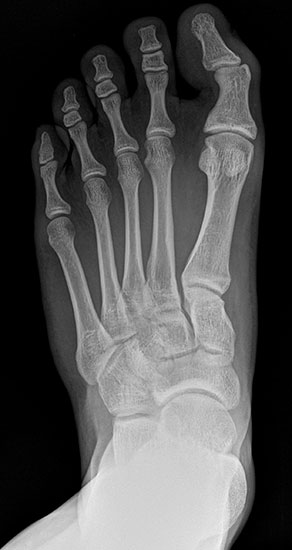

Röntgen

Standard ist die belastete Röntgenaufnahme des Fußes dorso-plantar und seitlich. Günstig ist eine Röhrenkippung von 10°-20°, um die Gelenke der Lisfranc-Linie einsehen zu können.

Ergänzend kann eine Schrägaufnahme hilfreich sein. Bei Metatarsalgien oder Pathologien der Sesambeine liefert die Sprinteraufnahme zusätzliche Informationen. Bei einer Pes planovalgus Fehlstellung wird ergänzend ein Saltzman view durchgeführt.

• Hallux valgus Winkel

• Hallux valgus interphalangeus Winkel

• Intermetatarsalwinkel I zu II

• Distaler Metatarsale Gelenkwinkel (PASA)

• Form des Mittelfußknochenkopfes

• Winkel Metatarsale I Basis zum Os cuneiforme mediale

• Metatarsalindex

• Elevation/ Plantarisierung I. Strahl

• Pes metatarsus adductus

• Wachstumsfugen

• Coalitiones

• Akzessorische Knochen